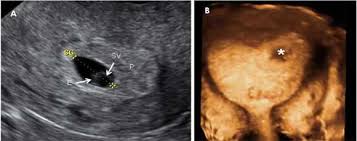

Un huevo huero se denomina cuando no es posible ver al embrión dentro del saco gestacional. Es muy frecuente sentir náuseas especialmente. De ahí la importancia de la suplementación de ácido fólico en el embarazo.

Embarazo Anembrionado Que Significa Madres Hoy